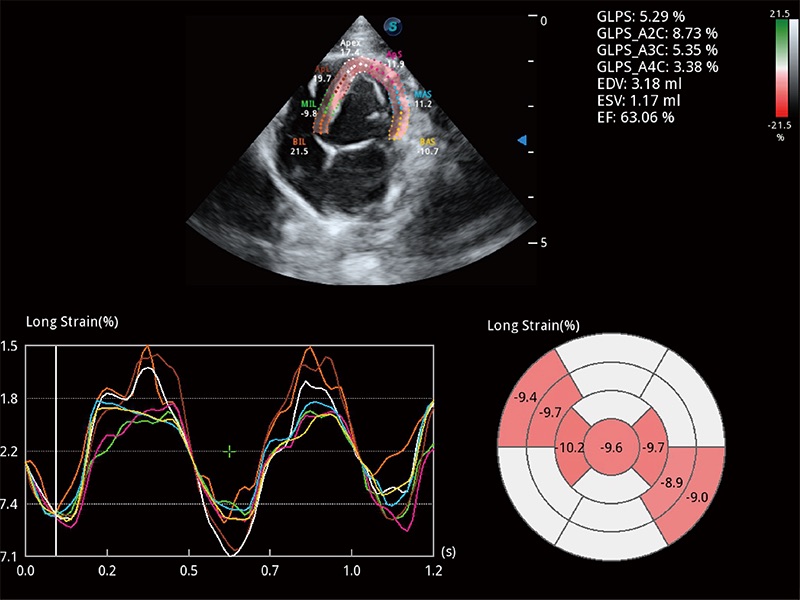

• MQA 心肌定量分析

通过心肌识别技术与二维斑点追踪技术相结合,对心脏的超声图像进行量化分析。计算心肌17个节段的应变、应变率、速度、位移等,并通过牛眼图的形式进行呈现。

• Auto EF 心内膜自动描迹

能够基于左心室壁追踪和辛普森法,自动计算射血分数,支持多个可移动点描迹,与手动测量相比,极大节省了动物医生的时间和精力。

(犬)四腔心MQA

(犬)二腔心血流